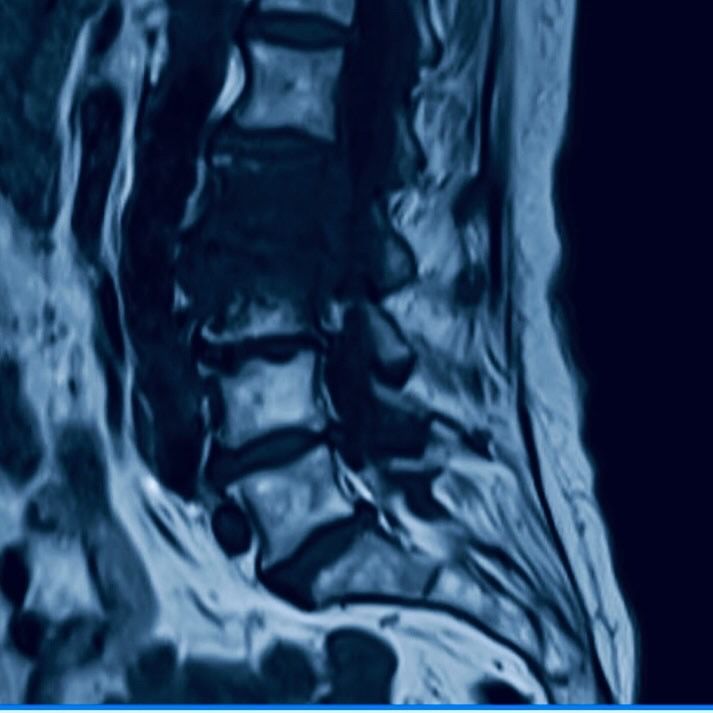

Como especialista em Neurocirurgia faço tratamentos de doenças relacionadas ao Sistema Nervoso Central como tumores, patologias vasculares, traumatismo e Infecções que necessitem de uma abordagem cirúrgica ou acompanhamento Clínico.

Sou especialista em Cirurgia da Coluna Vertebral e Medicina da Dor em que faço tanto tratamentos clínicos quanto cirúrgico.

• Lombalgia

• Cirurgia da Coluna Lombar

• Doenças Da Coluna Vertebral

• Hérnia de disco

• Deslocamento Do Disco Intervertebral

• Lombalgia (dor lombar)